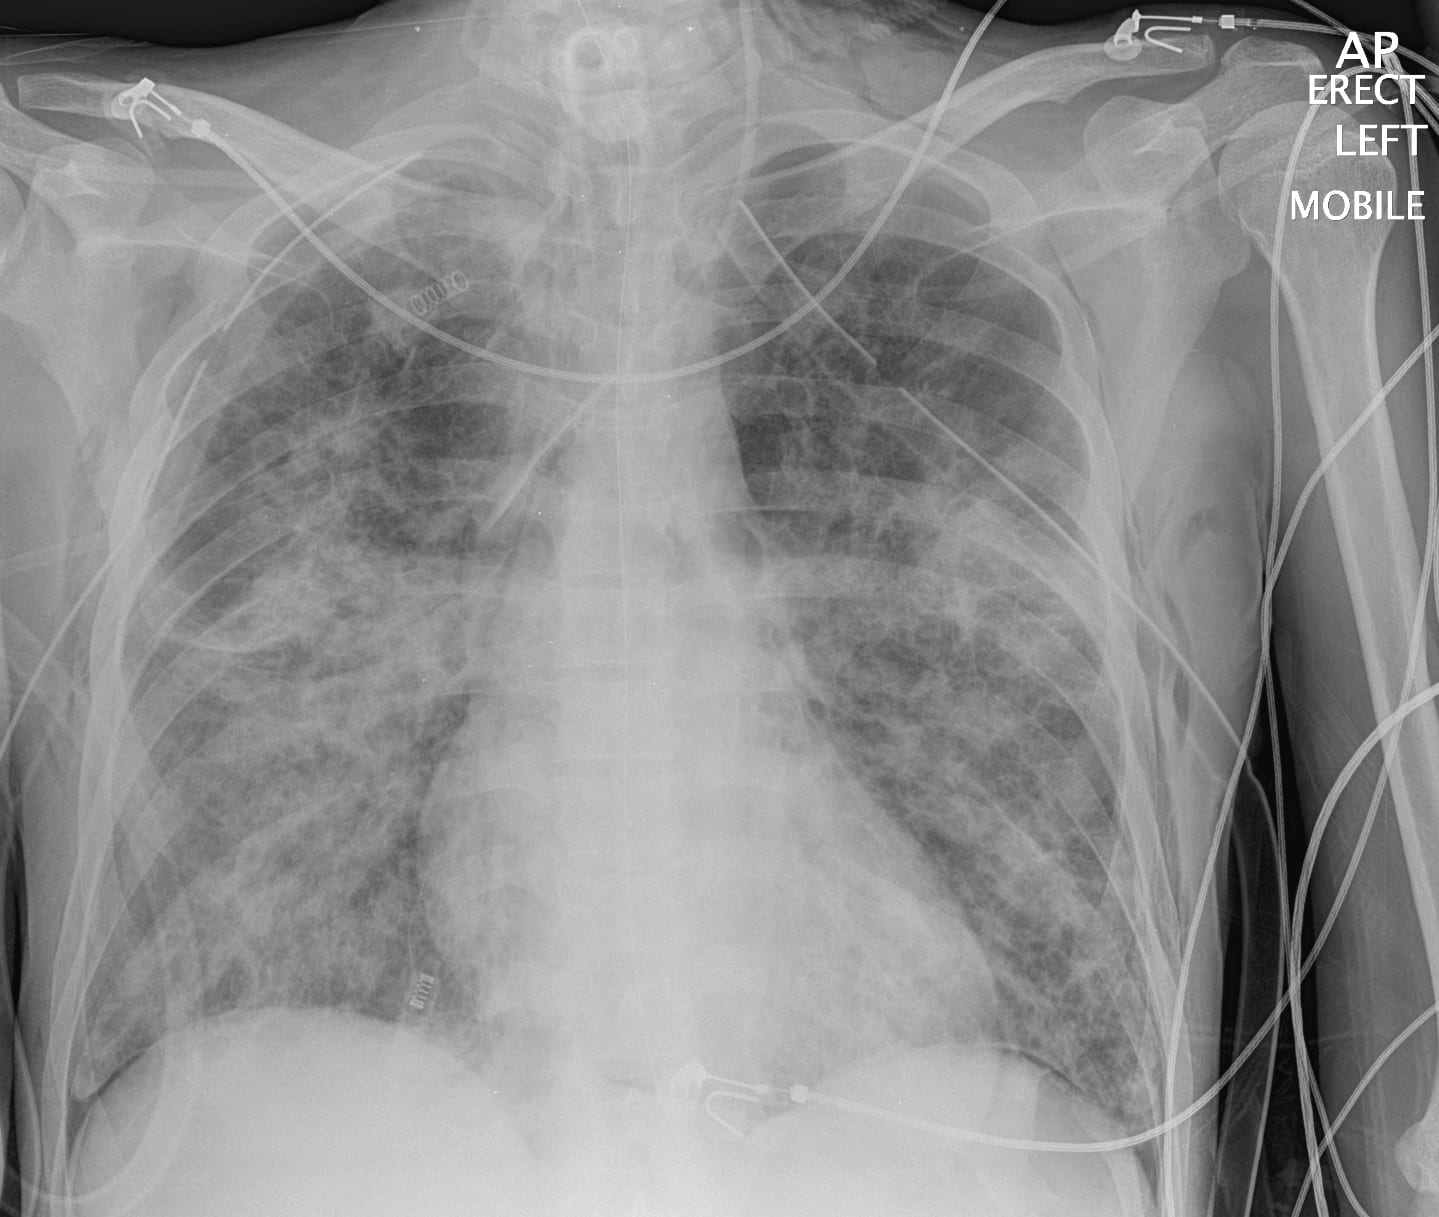

On A Chest X-Ray Emphysema Would Be Diagnosed By Quizlet . In this condition, millions of the lungs' tiny air sacs (alveoli) stretch out of shape. Destruction of alveoli and air trapping causes. The test cannot diagnose copd, but it can be used to find other conditions that. Only about half of patients with moderately severe copd can be diagnosed using chest. To diagnose copd, which includes chronic bronchitis and emphysema, your healthcare provider will review your symptoms, ask for your complete health history, conduct a physical exam. Emphysema is a respiratory disease. Chest radiograph has a poor sensitivity in diagnosing copd. What is the goal for emphysema?